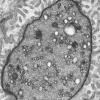

PERIPHERAL NEUROPATHY

3 NORMAL MYELIN & SCHWANN CELLS

2 Node of Ranvier